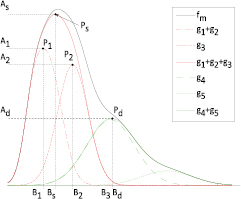

where the parameters aj, bj and cj correspond to the amplitude, location and width of the Gaussian function j. Here, the first two Gaussian functions ( ) correspond to the ventricular ejection and the third Gaussian function (g3) is related to the first pulse reflection at the junction between the thoracic and abdominal aorta, presented in figure 5. The fourth (

) correspond to the ventricular ejection and the third Gaussian function (g3) is related to the first pulse reflection at the junction between the thoracic and abdominal aorta, presented in figure 5. The fourth ( ) and fifth (

) and fifth ( ) Gaussian functions derive from the reflection at the juncture between abdominal aorta and common iliac arteries (Baruch et al 2011) and minor reflections and re-reflections in the systemic structure, respectively (see figure 5).

) Gaussian functions derive from the reflection at the juncture between abdominal aorta and common iliac arteries (Baruch et al 2011) and minor reflections and re-reflections in the systemic structure, respectively (see figure 5).

Figure 5. Representation of the multi-Gaussian model of a PPG pulse and individual Gaussian functions correspondent to the main forward wave and consequent reflections at the arterial pathway.  represents the main forward wave, consisting on the sum of

represents the main forward wave, consisting on the sum of  and

and  .

.